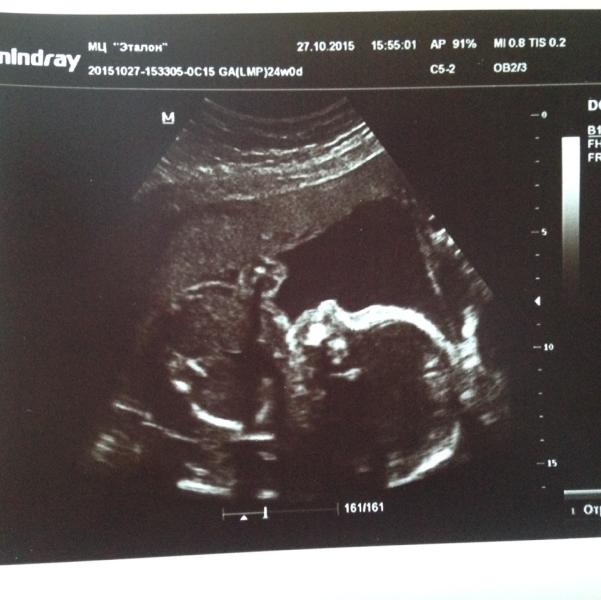

В 20 недель ездили на 2 скриннинг и из за того что я болела у малыша образовалась киста в голове, но сегодня ездили на досмотр и нам сказали что все у нас хорошо, подтвердили мальчика))

Наш маленький сынок)))